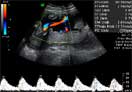

Doppler pulsado del cordón umbilical

En la parte inferior de la imagen se observa un trazado normal del flujo sanguíneo a través de la arteria umbilical (arriba).